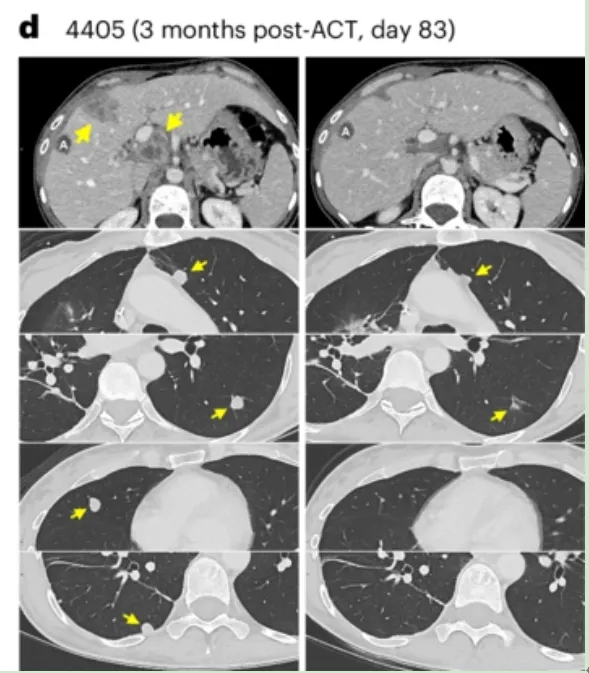

《Molecular Therapy》报道,Radium-1 TCR首次应用于1例林奇综合征(LS)合并晚期转移性MSI-HCRC患者。